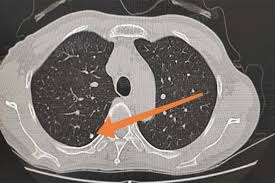

“双肺可见多发小结节影,大小约 2–5mm,边界清晰 / 模糊不等。”

定义:肺小结节是指肺内直径小于3厘米的类圆形密度影;

当结节直径 ≤6mm 时,称为“小结节”或“微结节”;

“多数 3–5mm 小结节都是良性的炎症残影。真正需要关注的,是那些‘单侧、毛刺状、在短期复查中长大的’结节。”

五、 “多发”≠“多癌”,CT 只是发现早、不是吓人多

现代高分辨 CT(HRCT)的分辨率极高,能看到0.2mm的结构,

所以检测出的“小结节”越来越多,并不代表肺癌发病率暴增。